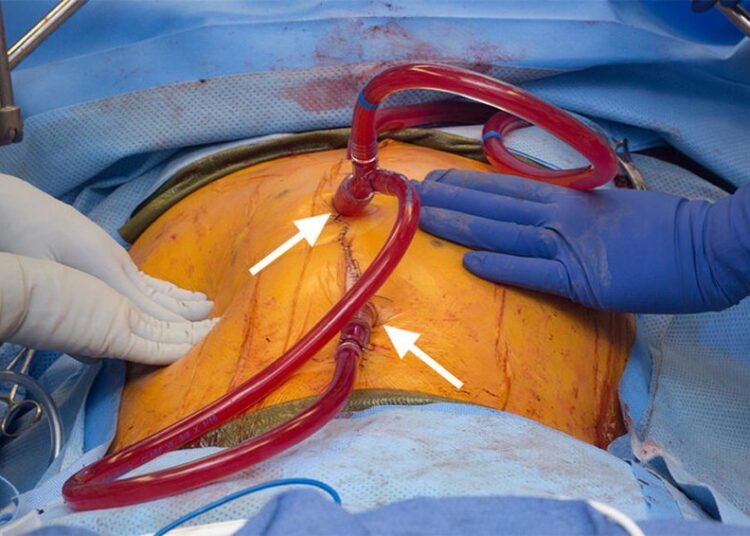

“Most cancer treatments have a chemotherapy component and some would involve a combination of surgery and chemotherapy. Generally, chemotherapy is either given as tablets or as an Intravenous medication (IV). This type of cancer usually occurs in appendix, colon, ovaries etc. At a stage where surgery alone won’t be enough, we recommend the HIPEC procedure. In this method, first the visible tumor cells are removed through surgery which is known as cytoreductive surgery. Thereafter a few tubes are inserted from the device that pumps the chemotherapy drug into the abdominal cavity at a heated temperature of 42 degrees Celsius which is monitored using an intra-abdominal temperature probe. This inflow of liquid goes on for 90 minutes, which impacts the micro cancer cells. We then remove the tubes, check for any bruises or bleeding in the abdomen and complete the procedure,” he adds.